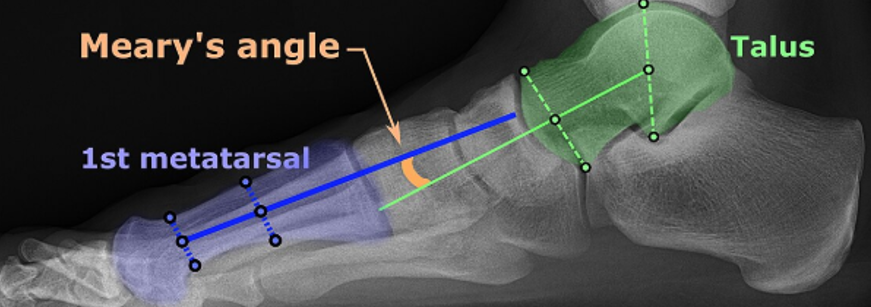

※ x-ray시 주요 각도 지표

♦거골-제1중족골각,Meary's angle(talus-1st metatarsal angle, TMA) : 정상범위 거의 0도부근( ±4도 이내), 4도이상시 평발이며 15°~30° 중등도, 30°이상시 중증으로 평가